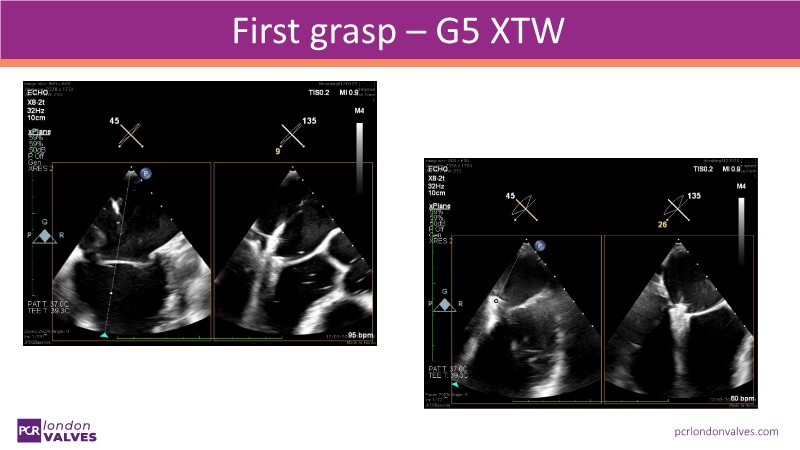

This LIVE case symposium brings mitral regurgitation guidelines into real clinical practice. Through step-by-step patient demonstrations and insightful discussion, the session explores how recommendations guide decision-making in ventricular and atrial secondary MR, how the heart team tailors therapy to individual anatomy and comorbidities, and how device iterations and procedural workflow can influence outcomes.